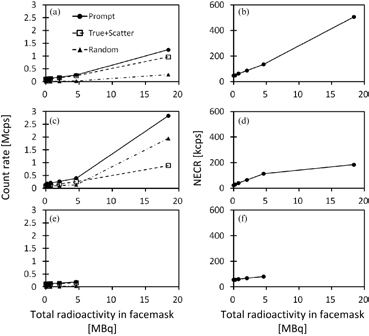

Standard image High-resolution imageFigure 4 shows counting-rate characteristics observed in the 3D brain-phantom experiment for each of cases 2, 3 and 4, namely the prompt, true + scatter and random events in the left column, as well as NECR in the right column, as a function of radioactivity inside the face mask. For the case 2 experiment, true rates increased when radioactivity in the face mask was increased almost linearly, as the random rates were small. NECR also increased almost linearly as the face-mask radioactivity was increased. In case 3, on the other hand, random rates were considerably increased compared with case 2. The random rates were even higher than the true + random rates, with the total radioactivity in the face mask being greater than 5 MBq. NECR in case 3 (figure 4(d)) tended to be saturated at the face mask radioactivity >5 MBq, and smaller than in case 1 (figure 4(b)). In case 4, the experiment was carried out only for a range of the face-mask radioactivity <5 MBq. The NECR shown in figure 4(f) reflect smaller values than in case 2 at the total radioactivity in the facemask <5 MBq.

Figure 4. Counting-rate characteristics as a function of radioactivity in the face mask observed in the 3D brain-phantom experiments for three different configurations of case 2 (a, d), case 3 (b, e) and case 4 (c, f), shown in figure 1. Figures a, c and e represent prompt, true + scatter, and random count rates for the three configurations and figure b, d, and f represent NECR.